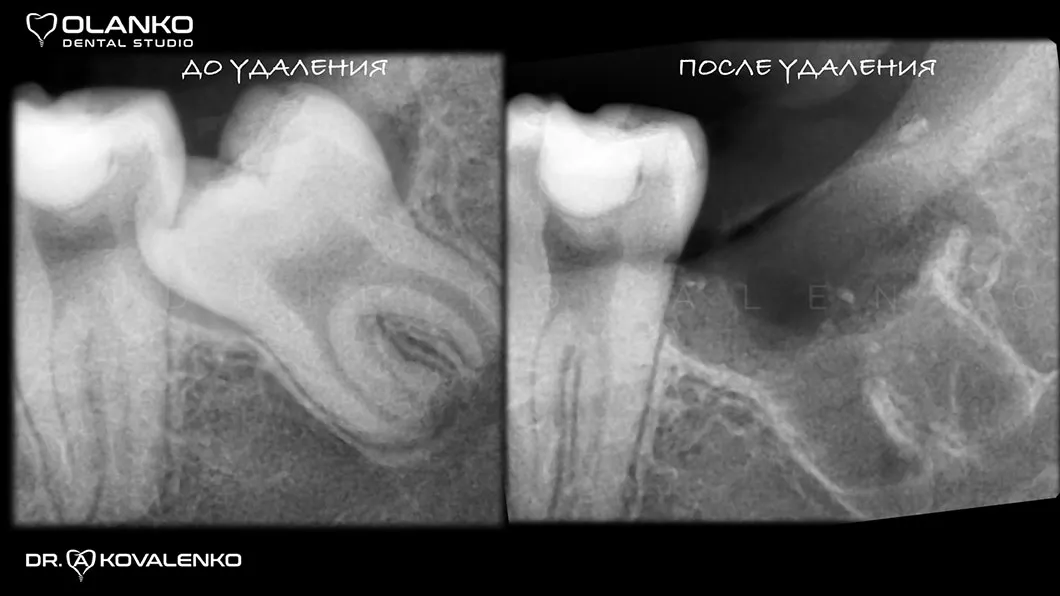

Фото рентген до та після видалення ретинованого зуба мудрості

Видалення складних зубів мудрості Оланко Бровари Київ